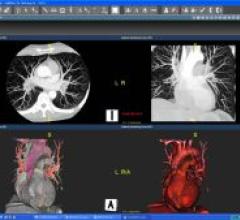

November 20, 2008 - TeraRecon Inc. released new innovations in the cardiovascular and vascular clinical applications for ...